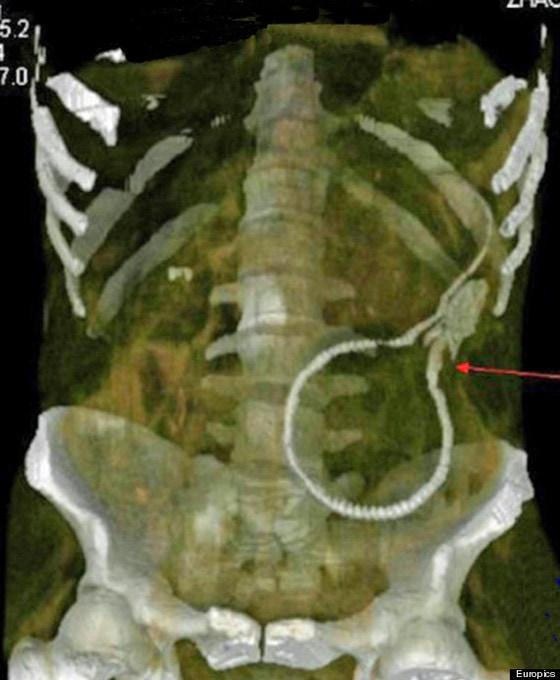

야동 흉내내다 항문으로 뱀장어 '쑥'

뱀장어

드렁허리